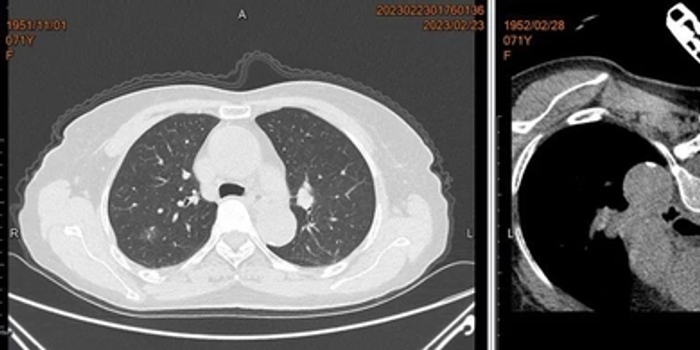

71岁的李阿婆,4月前体检发现肺部磨玻璃阴影,近日复查提示:原有病灶较前稍增大。

厦门大学附属中山医院呼吸与危重症医学科杜艳萍主任医师仔细询问患者病史,结合增强CT检查,考虑为恶性病变可能性极大。

杜艳萍主任医师带领呼吸科微创介入治疗团队,在CT精确定位下,利用微波消融针先行消融1分钟,活检留取标本送病理检查和基因检测,随后再行4分钟治愈性消融。

术后确认无气胸、炎症,第三天患者顺利出院。随访病理结果:原位癌。